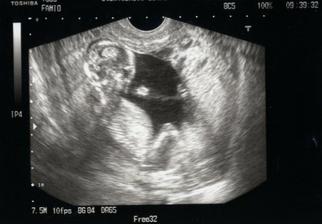

30.12.2009,13+5ttDnes jsem byla na kontrole, NT screeningu a I. UTZ. Miminko, vypadá nádherně, má se čile k světu a v bříšku si krásně hoví.

UTZ: CRL: 71mm, BPD: 26 mm

NT- 1,3